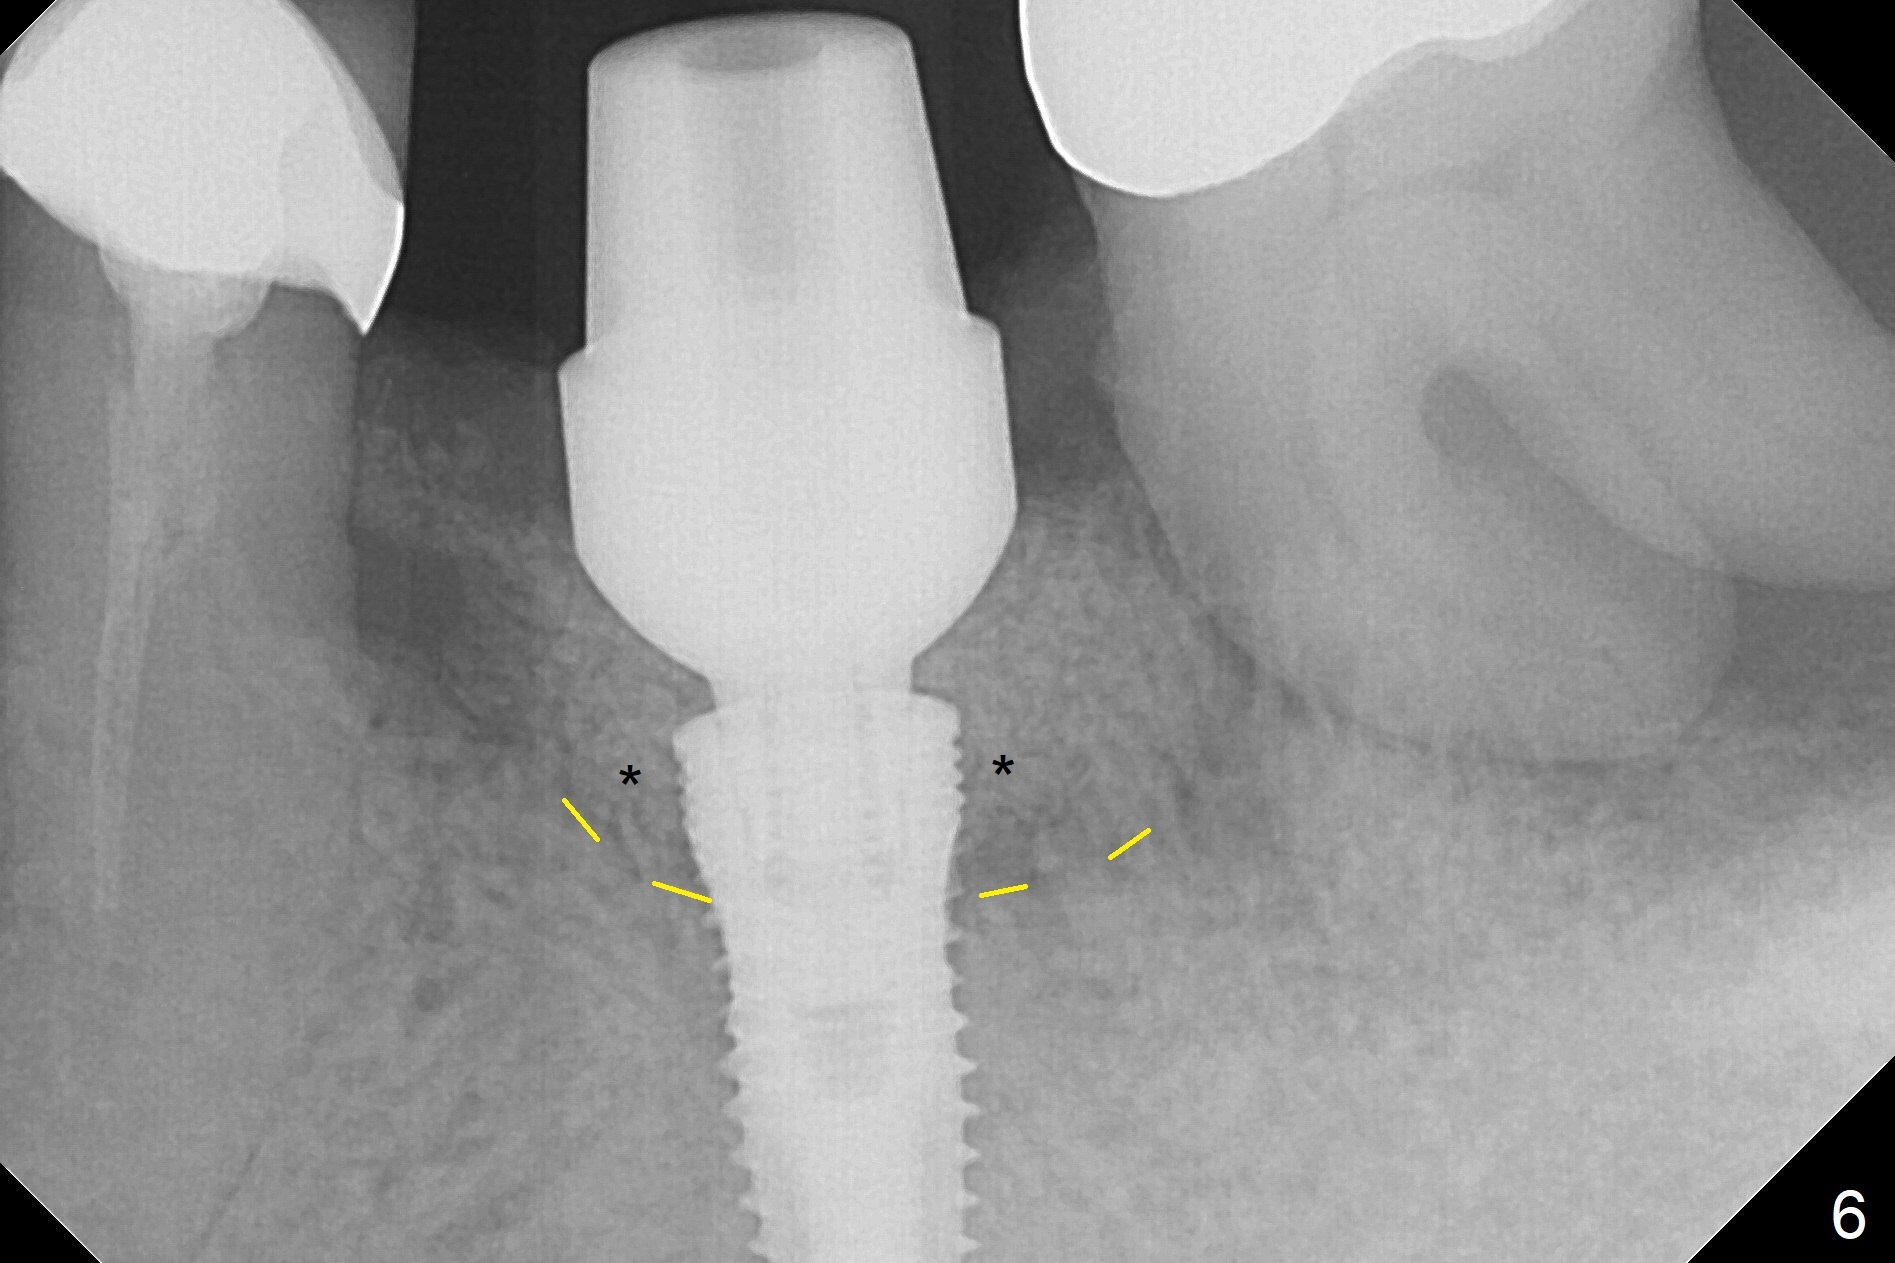

After extraction of the supraerupted tooth #19 with severe buccal gingival recession, the buccal and lingual plate are found to be lost. The sockets are fused and flat without the septum. The bone is hard and painful for the initial osteotomy with infiltration anesthesia (Fig.2). Following block anesthesia, the initial osteotomy depth extends to 8 mm (Fig.3,4). With apparent 4.9 mm clearance, the osteotomy is further extended to 10 mm. The osteotomy walls are apparently intact without severe hemorrhage after each drill. Due to the thick gingiva and severe bone loss, a 5x12 mm implant is intentionally placed 3 mm above the base of the socket bone (Fig.5,6 (yellow dashed line)). Vanilla Cortical and Cancellous allograft (Fig.6 *) is placed around the exposed implant and 7.8x5(6) mm abutment with 4 and 2 mm buccal and lingual gaps. Next collagen plug cut in strip is placed to fill the most coronal aspect of the socket (Fig.7 *). The buccal and lingual gingivae are approximated with sutures proximally. Finally periodontal dressing is applied. Since the Inferior Alveolar Canal is vague in intraop PAs (Fig.4,5), there is worry about potential nerve damage during and after osteotomy. This should be no issue if preop panoramic X-ray is reviewed with measurement (Fig.8). The bone graft appears to remain in place nearly 4 months postop (Fig.9). Two weeks later, he returns for impression. When the provisional is removed, the gingiva is unhealthy. Without the provisional and with improved oral hygiene, the gingiva is healthy one week later, but the tooth #18 is symptomatic. The latter is extracted with socket preservation (Fig.10 *). There is no apparent bone loss around the implant at #19 6.5 months post cementation (Fig.11).